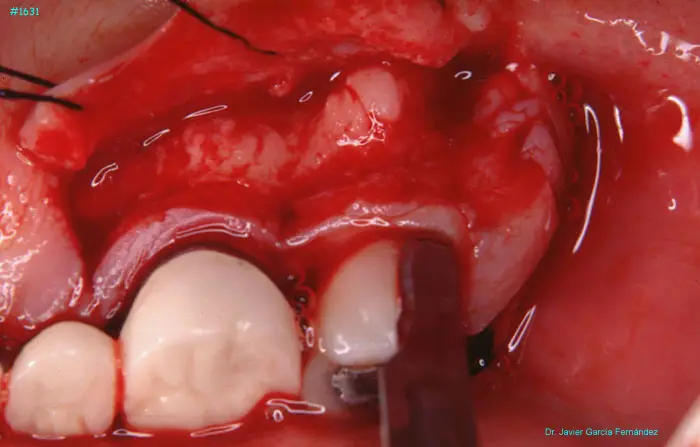

Atlas of Surgical Techniques in Periodontics. Chapter IV. Atlas de Técnicas Quirúrgica en Periodoncia

image 145